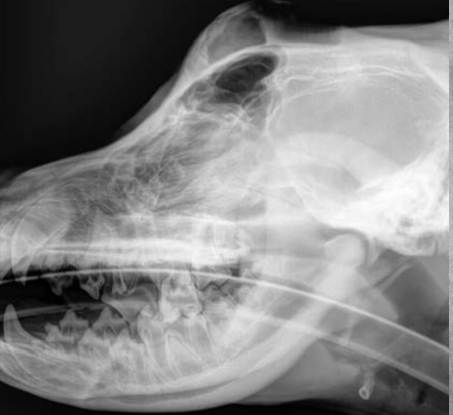

Review normal anatomy.

A